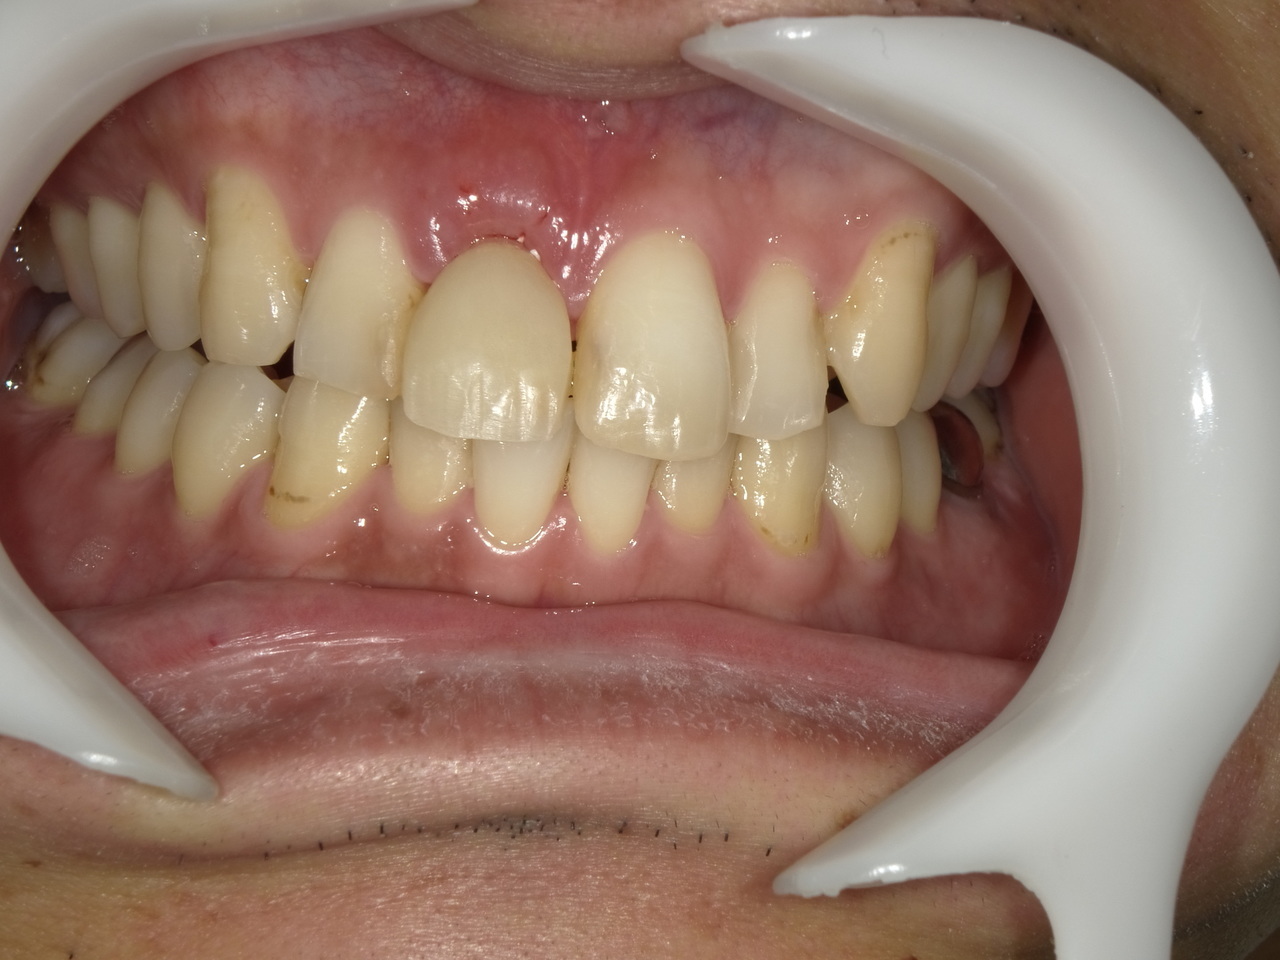

4.右上4~7番が重度に動揺しているために、抜歯した当日にインプラントを埋入して、3か月で最終的な歯を完成させたケース

After

枚方市のインプラントの症例

K・S様 女性 60代

症状としては、 右上4から7番までのすべての歯の著しい動揺があり、食事が困難であった。

治療法としては、患者様は、患者様が3か月以内の治療完了を望んでいたために、炎症が若干あったが、右上4から7番ぼすべての抜歯を行い、右上4番(抜歯即時埋入)、右上6番(上顎洞までの骨がほとんどないため、グラフトレスサイナスリフト施行)にインプラントを1回法で手術を終え、2か月半後にインプラントの状態が安定したために、3か月で上部構造の、右上456のジルコニアブリッジを装着して、治療を終えています。

治療結果としては、抜歯したと同時にインプラントを埋入することで、抜歯した穴が自然に治る過程で、インプラントの骨結合と組織の治癒が同時に行われるために、3か月という治療期間で治療を終了することができたことと、機能面・審美面でも回復を行うができた。また、右上6番に関しては、グラフトレスサイナスリフトを行うことで、従来のサイナスリフトに比べ、約9か月早く治療を終えることができました。

治療の期間・回数:約3か月、インプラント抜歯即時埋入から最終補綴物装着まで8回

治療の価格:792000円(税込)

治療費の内訳:インプラント基本料(フィックスチャー(メガジェンインプラントANYONE使用) 及び手術費用、投薬費用、レントゲン費用、インプラント上部費用(アバットメントおよびジルコニアクラウンの費用用)330000円×2 660000円(税込み)。オプション、抜歯即時埋入加算(人工骨費用を含まず)5500円×2 11000円(税込み)右上5ジル9コニアブリッジのポンテック費用 88000円 右上6グラフトレスサイナスリフト費用 33000円(税込み

治療のリスクや副作用:手術後に、痛みや腫れ、出血、合併症などを引き起こす可能性があります。噛む感覚がご自身の歯と異なる場合があります。見た目がご自身の歯と異なる場合があります。手術後にメインテナンスを継続しないと、インプラントが抜け落ちる可能性があります。